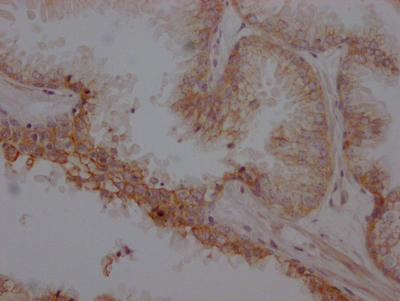

IHC image of CSB-RA286054A0HU diluted at 1:100 and staining in paraffin-embedded human prostate cancer performed on a Leica BondTM system. After dewaxing and hydration, antigen retrieval was mediated by high pressure in a citrate buffer (pH 6.0). Section was blocked with 10% normal goat serum 30min at RT. Then primary antibody (1% BSA) was incubated at 4℃ overnight. The primary is detected by a Goat anti-rabbit IgG polymer labeled by HRP and visualized using 0.05% DAB.